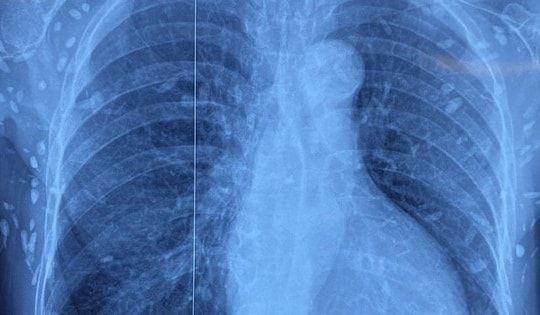

Chụp X-quang ngực cho người phụ nữ 77 tuổi, bác sĩ sốc nặng khi phát hiện "bí mật đáng sợ"

Người phụ nữ 77 tuổi được chuyển lên từ tuyến trước vì rối loạn ý thức đe dọa suy hô hấp, hình ảnh cắt lớp vi tính sọ não và X-quang ngực cho thấy rất nhiều nốt cản quang trong nhu mô não và dưới da vùng ngực-bụng.